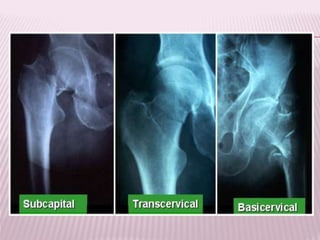

FRACTURAS CERVICALES

 Se subdividen en 3 tipos de acuerdo a la

localización anatómica de la fractura.

FRACTURA SUBCAPITAL

 Aquellas producidas en un plano

inmediatamente inferior al borde del cartílago

articular, generalmente tiene una orientación

oblicua de modo que compromete un

segmento pequeño de cuello del fémur.

FRACTURAS TRANSCERVICALES

 Compromete la parte media del cuerpo del

cuello femoral.

FRACTURA TRANSCERVICAL

FRACTURA BASICERVICAL

 El trazo de fractura coincide con el plano de

fusión de la base del cuello en la superficie

interna del macizo trocantereo.